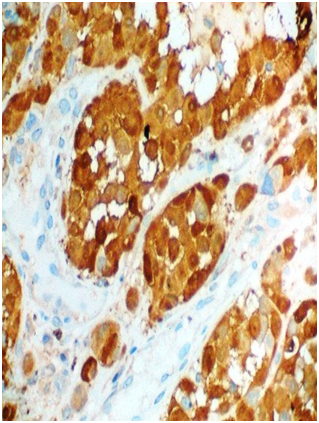

A 53-year-old female presented with one-month history of gross hematuria and increased frequency of urination. There was no past history of calculus. She did not have any medical comorbidities. She underwent hysterectomy after last childbirth at the age of 40 years. General physical examination and routine blood investigations were normal. CECT scan of whole abdomen showed 4.4x3.7x2 cm polypoid enhancing mass in urinary bladder with bladder wall thickening. Cystoscopy revealed blackish solitary papillary growth near bladder neck from 10 o’clock to 2 o’ clock position. A transurethral resection of the lesion was performed including deep muscular layers of the bladder wall. The respected specimen examination showed pigmented melanocytes infiltrating sub epithelial tissue below the transitional epithelium (Figure 1). Margins of resection were free, however, base was involved. Atypical melanocytes were seen at the margins of the tumor. Immunohistochemical study showed that tumor cells were positive for S-100 (Figure 2) and HMB-45 (Figure 3). They were negative for cytokeratin and SMA. Dermatologic, ophthalmologic, otorhinolaryngologic and proctologic evaluations were negative. Upper gastrointestinal endoscopy and colonoscopy were negative. Abdomen, chest and brain CT scans were negative. Bone scan was negative. These findings were consistent with primary malignant melanoma of urinary bladder. After thorough review of published scientific literature, we suggested radical cystectomy as the therapeutic option. The patient declined any further treatment so was given only symptomatic & supportive treatment. Nine months later, she presented with hematuria and back pain. PET-CT showed increased uptake in lumbosacral vertebrae and liver, suggestive of metastases. She was advised palliative radiotherapy to the painful bone metastases and continued to receive palliative care. She succumbed to complications caused by widespread metastases fourteen months after the diagnosis.

Clinical examination was negative for cutaneous lesion and there was no history or evidence of regressed melanomas. CT scans of abdomen, chest & brain at diagnosis were essentially normal. The immunohistochemical markers HMB-45 antigen & S-100 protein became important components of diagnosis.6 In our case, HMB-45 and S-100 immunostaining were positive for tumor cells.

Malignant melanoma of bladder is rare. Criteria reported by Ainsworth5 are the most acceptable guidelines to confirm the diagnosis. A careful review of histological features and performing immunohistochemical-staining procedures for S-100 and HMB-45 are very important in confirming the diagnosis. Due to rarity of the tumor no standard treatment guidelines are available. Most of the patients in literature were treated as melanomas of other commoner sites are treated.